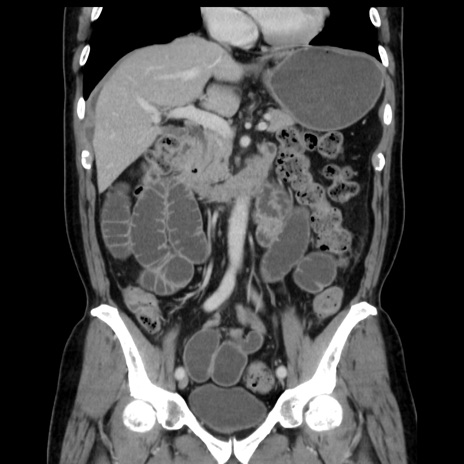

症例16(冠状断像)

【症例】 70歳代男性

【主訴】 腹痛、嘔吐

【現病歴】 約1ヶ月前より間欠的に腹痛と嘔吐あり、当院消化器内科を受診したところCTで多発する肝臓のLDAを指摘され、精査中であった。以降は消化器症状は安定していたが、2日前より嘔気と腹痛があり、同日より排便・排ガスが消失した。改善認めず、 本日、救急外来を受診した。

【既往歴】 大腸ポリープ切除後。

【身体所見】意識清明・会話良好、BT 36.3℃、BP 127/80mmHg、 P 80bpm、腹部:膨満あり、平坦・軟、上腹部正中および下腹部正中に圧痛あり、反跳痛なし、筋性防御なし。

【データ】WBC 7200、CRP 0.77